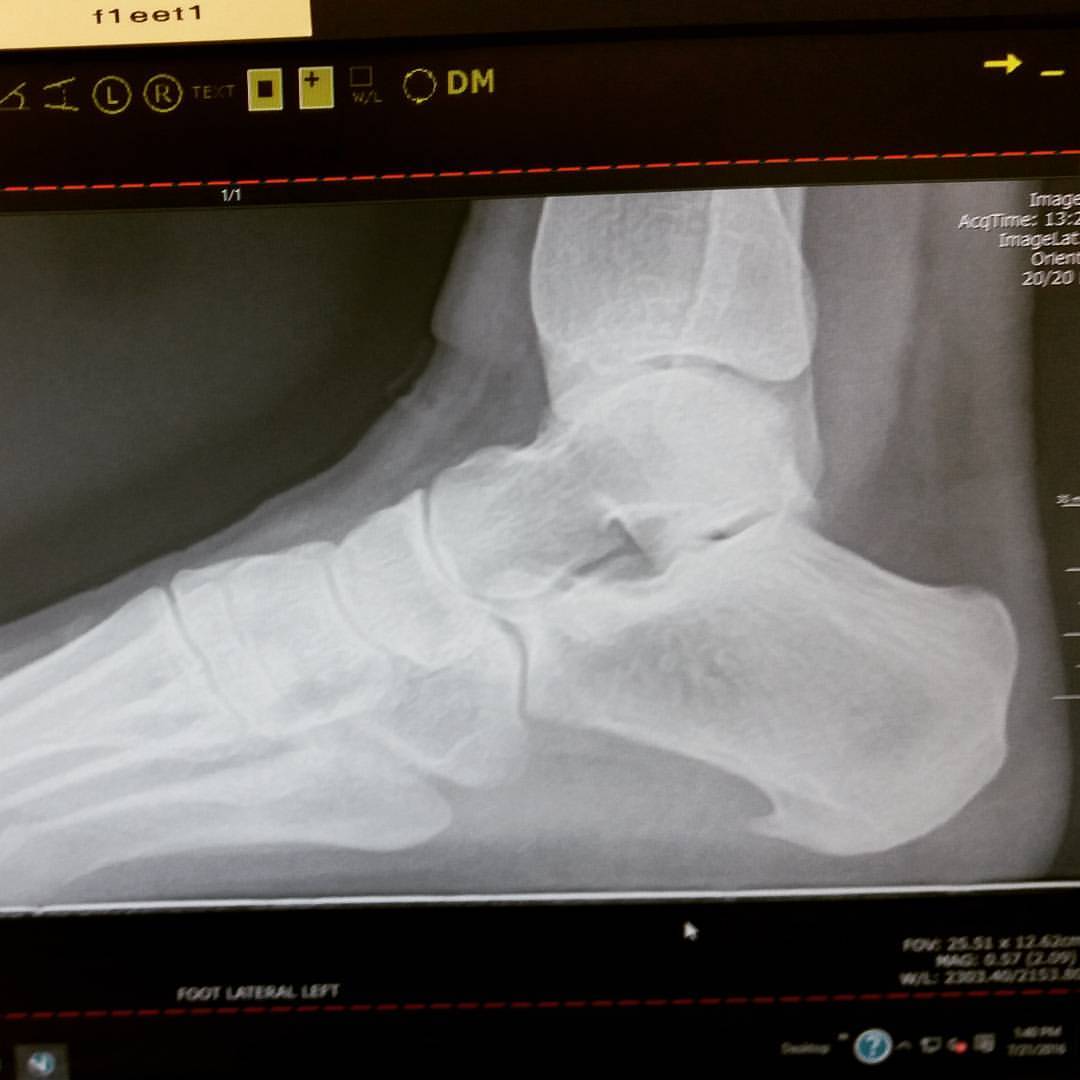

![]() |

| See that hook at the bottom? Not supposed to be there. |

Also, my podiatrist pointed out to me that the Xrays also showed that my feet are structurally unsound, (ie, my feet are pretty, just not built well) which means that my arches are starting to collapse. The extra weight I’ve put on these past five years (in my defense, about half of that is muscle) isn’t helping.